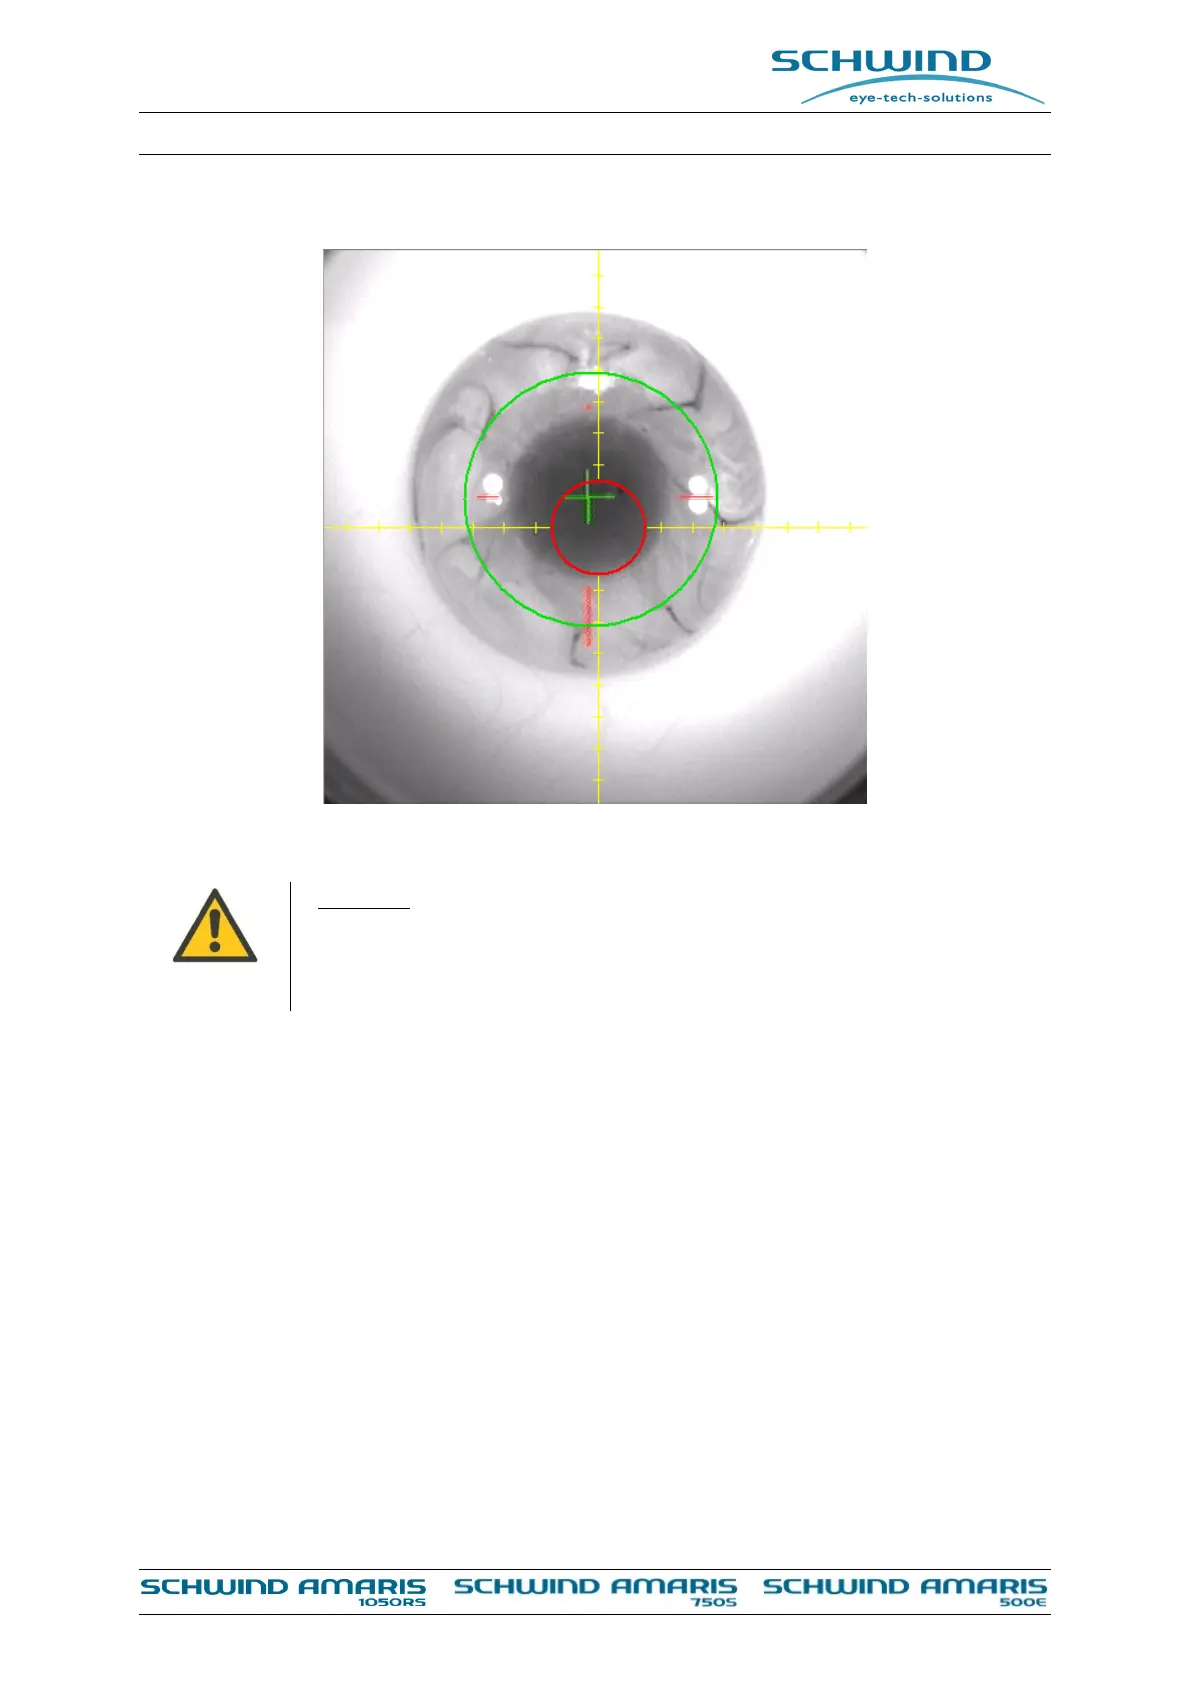

Figure 8-9: Arrangement of the coordinate system for the eye tracker

The arrangement of the coordinate system is displayed in Figure 8-9. Positive

values along the x-axis point to the right side of the patient and positive values

along the y-axis point in the direction of the patients head.

The eye tracker calculates the center of the pupil from the live picture. This point of reference is

represented on the screen with a RED CROSS. The red crosshair indicates the deviation of the pupil

center from the center of the beam path by changing the length of its axis.

In case of the asymmetric offset, a GREEN CROSS represents the deviation from pupil centre

including offsets from Rolling and PCSC (Pupil Center Shift Compensation). The Total Ablation

Zone (TAZ) is displayed dynamically as a GREEN COLOURED CIRCLE following the position of the

ablation center (not displayed) which is equal to the pupil centre (RED CROSS).

In case of the symmetric offset, a GREEN CROSS represents the deviation from pupil centre

including offsets from Rolling and PCSC (Pupil Center Shift Compensation). Here, shift of the

GREEN CROSS due to a possibly symmetric offset is excluded in this display. The Total Ablation

ablation center (not displayed) with regard to the pupil centre (RED CROSS) and the symmetric

offset magnitude of the SCHWIND CAM treatment plan.

Note: In both symmetric and asymmetric offsets the pupil center without Rolling and PCSC is

visualized by the RED CROSS. The GREEN CROSS always denotes the pupil center including offsets

from Rolling and PCSC whether the asymmetric or the symmetric offset strategy is selected and

+ X

+ Y